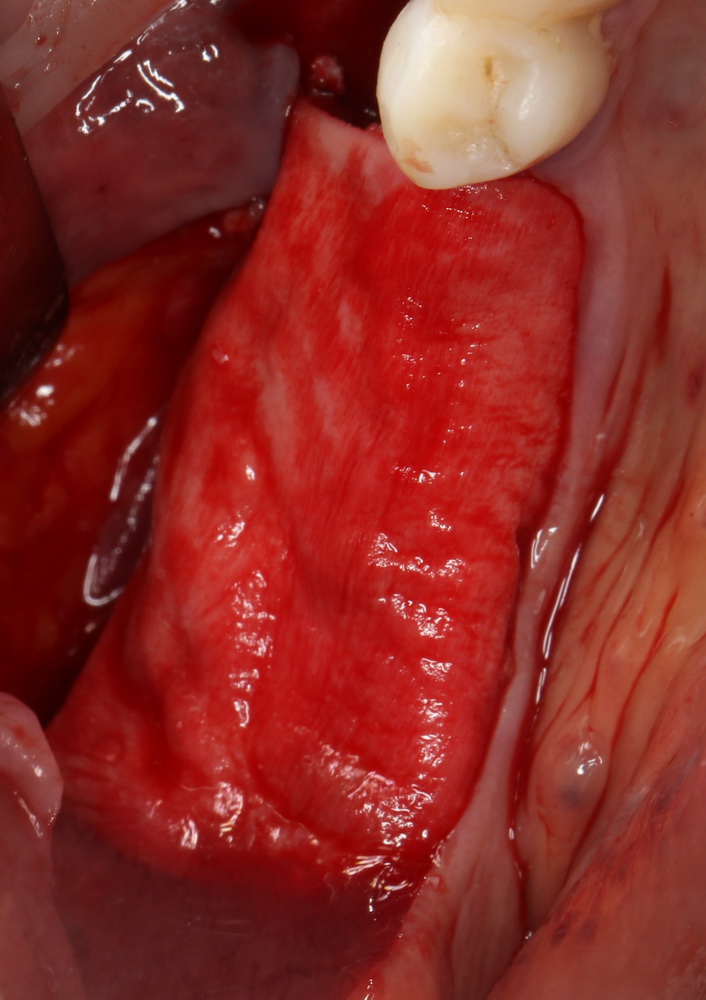

Продолжим нашу работу. Имплантат установлен:

Работа закончена? Отнюдь, нет. Теперь наша задача — восстановить утраченные объемы костной ткани вокруг импланта. Ибо, как вы видите на фото, его вестибулярная поверхность, практически, просвечивает. И, если ничего не делать, дальше будет только хуже.

Какой способ выбрать для остеопластики? Вспоминаем формулу: